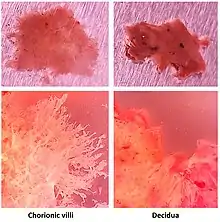

Products of conception, abbreviated POC, is a medical term used for the tissue derived from the union of an egg and a sperm. It encompasses anembryonic gestation (blighted ovum) which does not have a viable embryo.

In the context of tissue from a dilation and curettage, the presence of POC essentially excludes an ectopic pregnancy.

Recent studies indicate that the products of conception may be susceptible to pathogenic infections,[7] including viral infections. Indeed, footprints of JC polyomavirus and Merkel cell polyomavirus have been detected in chorionic villi from females affected by spontaneous abortion as well as pregnant women.[8][9] Another virus, BK polyomavirus has been detected in the same tissues, but with lesser extent.[8]